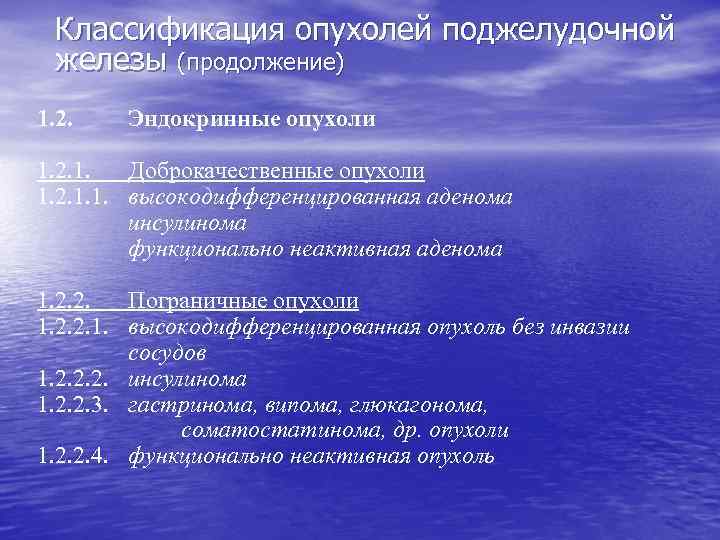

Классификация опухолей поджелудочной железы (продолжение) 1. 2. Эндокринные опухоли 1. 2. 1. Доброкачественные опухоли 1. 2. 1. 1. высокодифференцированная аденома инсулинома функционально неактивная аденома 1. 2. 2. Пограничные опухоли 1. 2. 2. 1. высокодифференцированная опухоль без инвазии сосудов 1. 2. 2. 2. инсулинома 1. 2. 2. 3. гастринома, випома, глюкагонома, соматостатинома, др. опухоли 1. 2. 2. 4. функционально неактивная опухоль